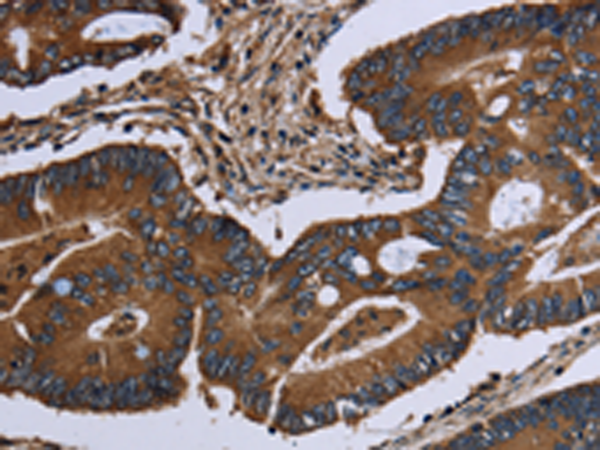

IHC positive control:

Human colon cancer and human lung cancer

IHC Recommend dilution:

50-200